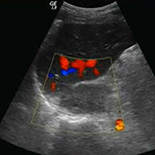

The purpose of this study was to define the ultrasound imaging characteristics of adrenal tumors and to assess the performance of ultrasound in differentiating benign ‘leave-alone’ lesions from suspicious lesions.

We enrolled 882 patients in this study. The nature of each lesion was determined by histopathology. Ultrasound finding of each lesion was compared with its corresponding histopathologic result. The final study group consisted of 911 adrenal masses in 882 patients. All images were reviewed by 2 experienced investigators in a double blind manner.

There were 553 adenomas identified in the study, which constituted 60.70% of the lesions. There were 161 pheochromocytomas (17.67%), 49 myelolipomas (5.38%), 39 cysts (4.28%), 37 metastasis (4.06%), 35 ganglioneuromas (3.84%), 22 lymphomas (2.41%), and 15 cortical carcinomas (1.65%). The sensitivity, specificity, and accuracy of ultrasound-based diagnosis were 89%, 99%, and 93.9%, respectively. A positive predictive value of 90.9% and a negative predictive value of 94.2% were obtained in this study.

This large-sample study showed that ultrasound was a reliable method in differentiating benign ‘leave-alone’ lesions from suspicious lesions.